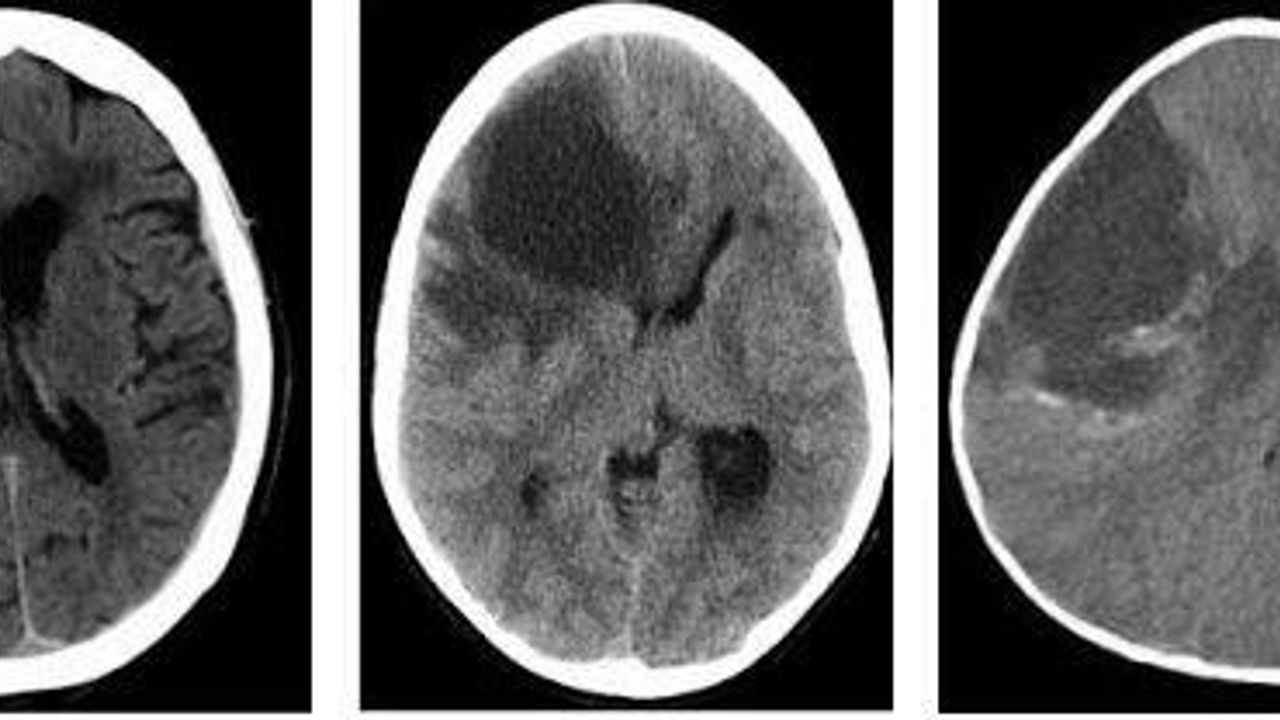

Hipodens terimi, çoğunlukla bilgisayarlı tomografi sonuçlarında kullanılan ve düşük yoğunluk anlamına gelen bir ifadedir. Görüntüleme sırasında normal dokulara göre daha az yoğun görülen alanlar hipodens olarak tanımlanır. Bunun yanında hiperdens ve izodens gibi kavramlar da yoğunluk farklarını belirtmek amacıyla kullanılır.

Tomografi ve MR incelemelerinde patolojik ya da normal dışı yapıların ayırt edilmesi için yoğunluk ölçümleri yapılır. Bu yöntemle normalden farklı görünen alanların saptanması ve değerlendirilmesi sağlanır. Hipodens lezyon saptanması, her zaman hastalık anlamına gelmeyebilir. Bazı durumlarda bu alanlar klinik olarak anlam taşımayabilir.

Hipodens lezyon tanısı, çoğunlukla bilgisayarlı tomografi ve MR gibi görüntüleme yöntemleriyle konur. Karaciğerde saptanan hipodens alanlar, yağlanma, kist ya da farklı doku değişiklikleriyle ilişkili olabilir. Gerekli görülen durumlarda patolojik inceleme yapılarak lezyondan örnek alınabilir. Bu incelemeler sonucunda lezyonun iyi huylu ya da kötü huylu olduğu belirlenir ve tedavi planı buna göre oluşturulur.